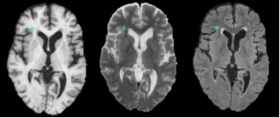

Predicted Heat Map, Manual Segmentation, Thresholded Heat Map

• The method makes use of local morphometric features based on multiple MR sequences, including T1-weighted, T2-weighted, and Fluid Attenuated Inversion Recovery. After preprocessing, including co-registration, brain extraction, bias correction, and intensity standardization, 49 features are calculated for each brain voxel based on local morphometry. At each level of segmenta- tion a supervised classifier takes advantage of a different subset of the features to conservatively segment lesion voxels, passing on more difficult voxels to the next classifier. This multi-level approach allows for a fast lesion classification method with tunable trade-offs between sensitivity and specificity producing accuracy comparable to a human rater.